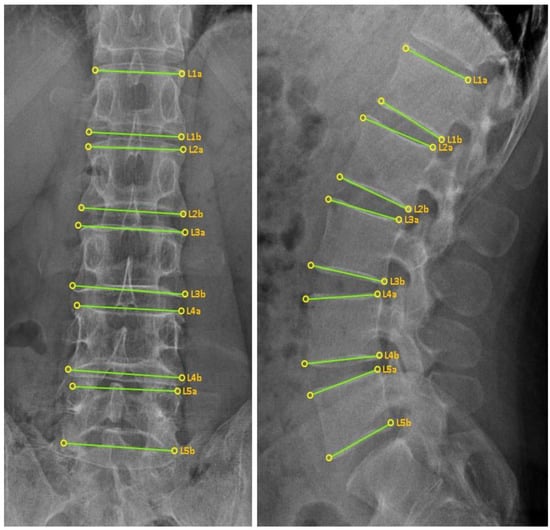

2.6.4. CMT X-ray Image-Based Diagnostic Method Using the CMT-AI Program